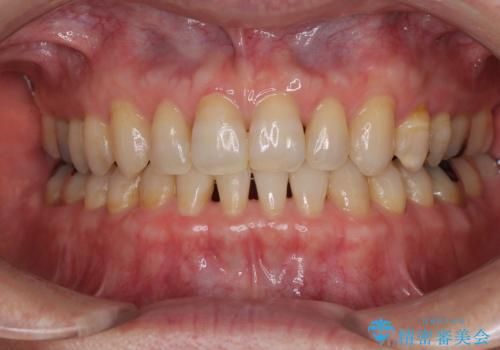

捻れて前に出ている前歯 ワイヤー装置での非抜歯矯正